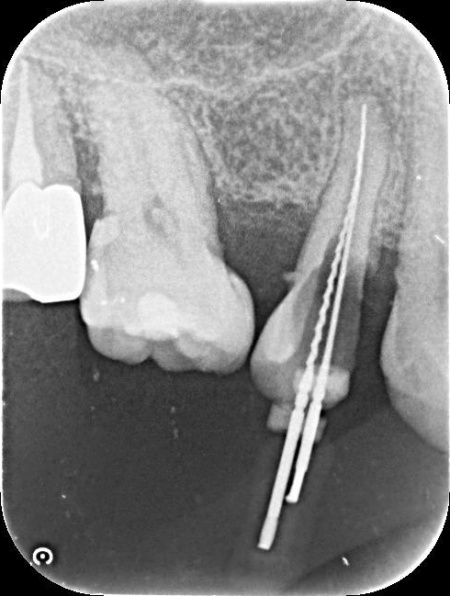

レントゲン撮影で詳しく検査した結果、虫歯が神経まで進行しており、歯根の先に黒い影が確認できます。 このまま放置すると、炎症が広がって歯を支える骨が溶けるおそれがあるため、早急に治療をする必要があると診断しました。 |

| 行ったご提案・治療内容 | 患者様は、歯をできるだけ残したいと希望されています。 そのため、感染した神経を取り除いて歯根内部を清掃・消毒する「根管治療」を行い、歯全体を覆う被せ物を装着する方法を提案し、同意いただきました。 メリット デメリット まず、根管治療で神経を慎重に取り除き、根管内の清掃と消毒を行います。 次に、歯を保護するための被せ物「ジルコニアクラウン」を装着します。 最後に、痛みや違和感がないか、問題なく噛むことができるかを確認し、治療を終了しています。 |

治療中